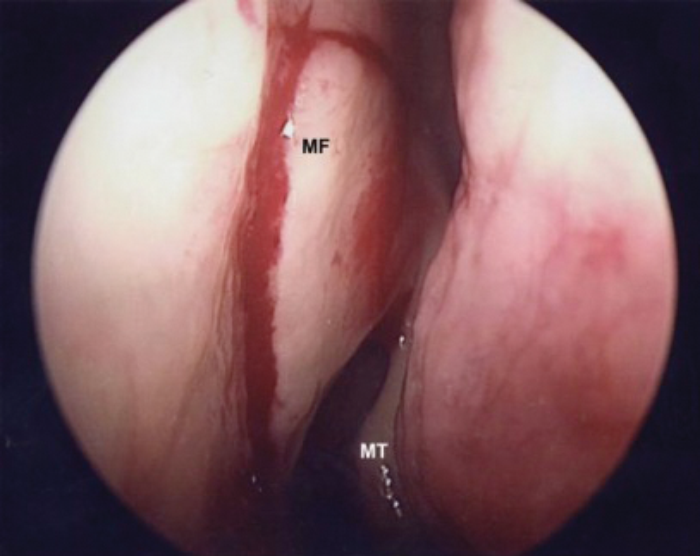

Endoscopic Dacryocystorhinostomy

Epiphora, or abnormal tearing, occurs because of blockage in the lacrimal drainage system, which impairs normal tear channeling into the nose. Dacryocystorhinostomy (DCR) is used to treat patients diagnosed with lacrimal sac or nasolacrimal duct obstruction (NLDO). External DCR was...